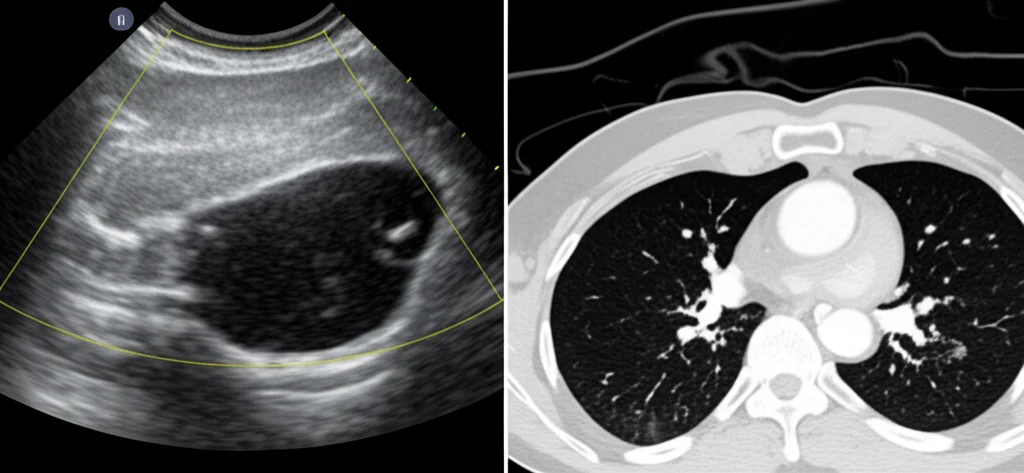

Parlo dell’ecografia polmonare point-of-care, o per gli amici, PoC-LUS (Point-of-Care Lung Ultrasound). Immaginate un ecografo, simile a quello usato per vedere i bambini nella pancia della mamma, ma spesso più piccolo, portatile, che noi medici d’urgenza usiamo per scrutare i polmoni. Niente radiazioni, niente spostamenti complicati del paziente magari instabile, risposta quasi immediata. Sembra troppo bello per essere vero? Beh, tenetevi forte.

Di recente, mi sono imbattuto in uno studio prospettico osservazionale, un “pilot”, condotto in un grande ospedale universitario in Romania tra il 2022 e il 2024. L’obiettivo era semplice ma cruciale: confrontare la diagnosi fatta da noi medici del PS – basata su anamnesi, visita, analisi dei gas nel sangue (emogasanalisi o EGA) e, appunto, la PoC-LUS – con la diagnosi finale, quella fatta dai medici specialisti al momento del ricovero, che include anche esami del sangue completi, la famigerata TAC toracica (considerata il gold standard) e altre valutazioni specialistiche. In pratica, hanno messo a confronto la nostra valutazione rapida “al fronte” con quella più ponderata e completa “nelle retrovie”.

Il nostro lavoro in PS è una lotta continua contro il tempo e il sovraffollamento. I reparti di radiologia sono spesso intasati, le attese per una radiografia del torace (che peraltro ha una sensibilità e specificità non eccezionali per molte cause di dispnea) o una TAC possono essere lunghe. La TAC è fantastica, è vero, ma è costosa, usa radiazioni ionizzanti e richiede che il paziente venga spostato, cosa non sempre facile o sicura se è instabile.

- È accurata: come dimostrato dallo studio, l’accuratezza è paragonabile a quella della TAC per molte patologie.